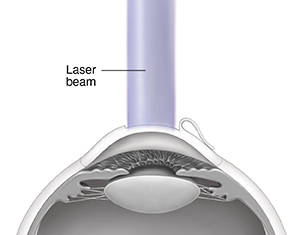

LASIK stands for laser in-situ keratomileusis. It's a technique for reshaping the cornea. It helps you see better without glasses or corrective lenses. This procedure uses an excimer laser that makes a concentrated beam of ultraviolet (UV) light. Each pulse of the laser can remove a tiny part of corneal tissue. LASIK can be used to correct the following conditions:

Your surgeon uses a computer-guided excimer laser to reshape the cornea. The laser treatment part of the procedure lasts for 10 to 90

seconds.